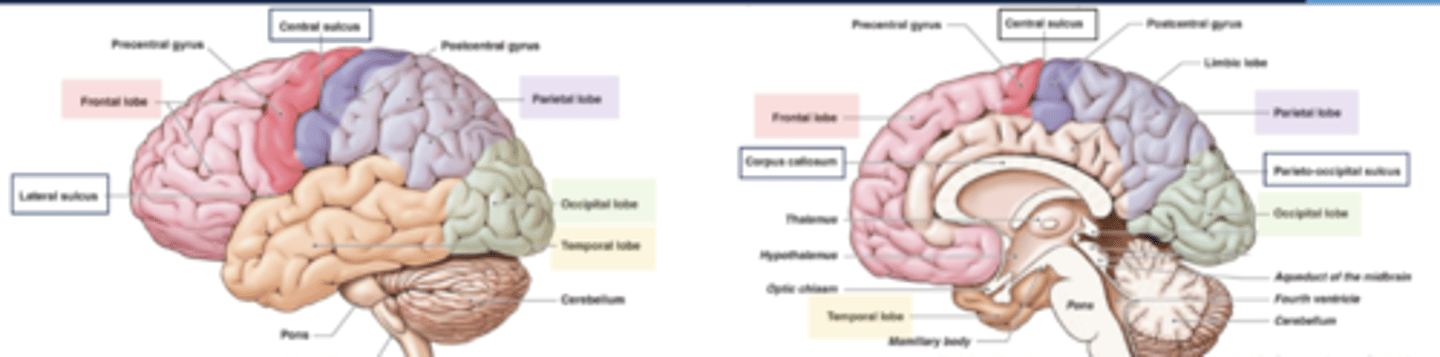

list the functions of the frontal lobe:

1. movement

2. executive functions

3. problem solving

4. reasoning/judgement

5. behaviors (emotions)

6. language production

7. memory

list the functions of the parietal lobe:

1. sensation

2. body orientation

3. spatial relationships

~primary somatosensory cortex~

list the functions of the temporal lobe:

1. language comprehension

2. hearing

3. behavior

4. memory

list the functions of the occipital lobe:

1. vision

2. color perception

list the cortical region and cerebral lobe of the somatic motor system/primary motor cortex:

cortical region:

precentral gyrus

cerebral lobe: frontal (M1)

list the cortical region and cerebral lobe of the somatosensory system/primary sensory cortex:

cortical region:

postcentral gyrus

cerebral lobe: parietal (S1)

what are the boundaries of the frontal lobe?

central sulcus and lateral fissue

what are the boundaries of the parietal lobe?

central sulcus, lateral fissure, parieto-occipital sulcus

what are the boundaries of the occipital lobe?

parietal-occipital sulcus

what are the boundaries of the temporal lobe?

lateral fissure